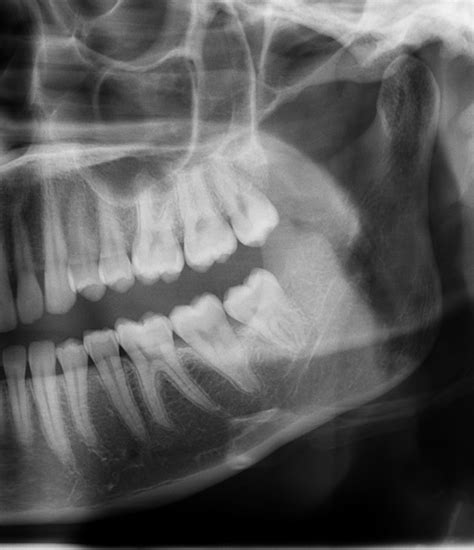

• Impacted Teeth: When the tooth is stuck beneath the gum line or bone, it creates a space where bacteria easily collect.

Maintaining excellent oral hygiene remains your best defense. Even if your wisdom teeth are currently healthy, using a single-tufted toothbrush can help you reach behind the last molars, effectively removing plaque that a standard toothbrush might miss. Regular dental check-ups, including necessary X-rays, allow your dentist to monitor the position of these teeth and predict potential issues before they escalate into an painful abscess.